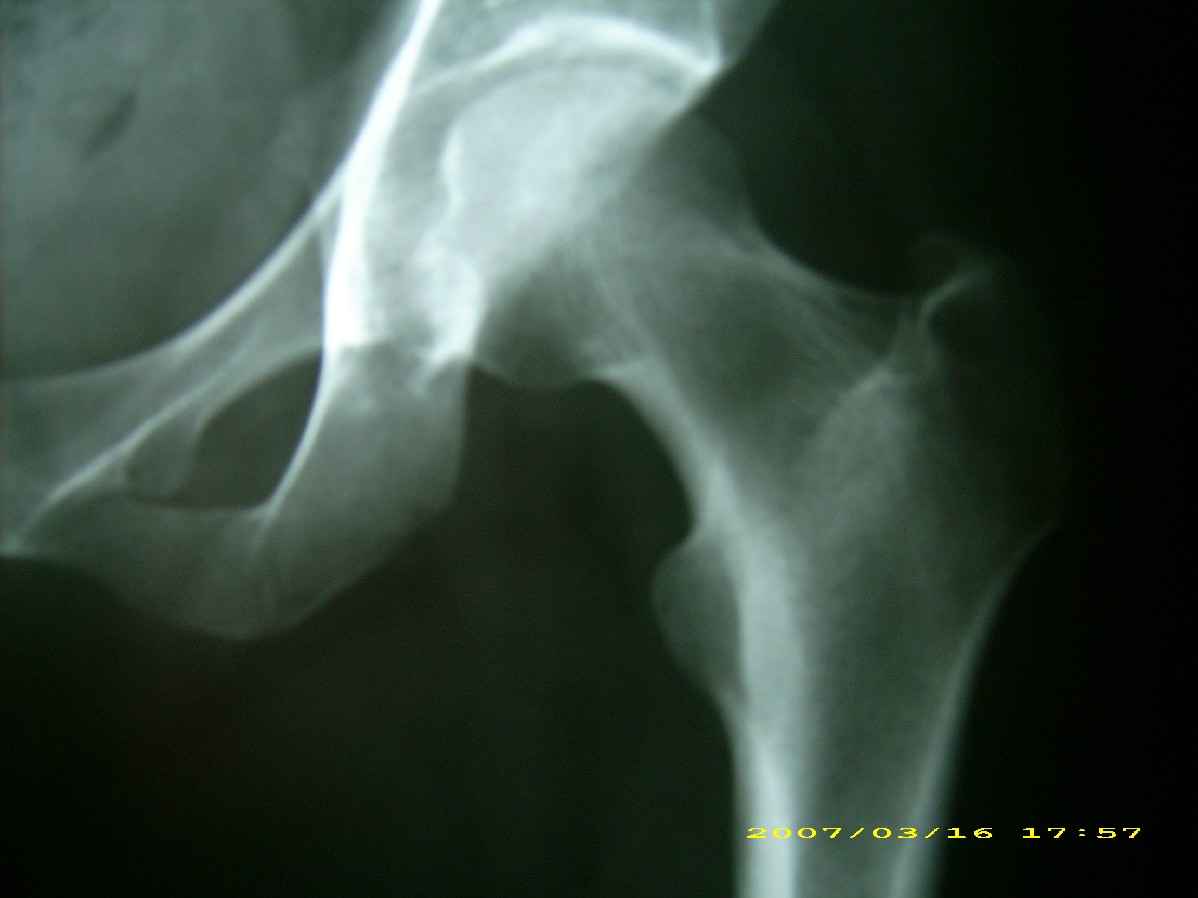

患者,女,因外伤就诊。摄骨盆及右股骨。当时报告骨盆未见明显异常,右股骨中段粉碎性骨折。五天后行股骨中段骨折内固定手术,术中摄床边片示股骨颈骨折。现把术前和术中图像上传。请大家高诊,分析股骨颈骨折是术前漏诊还是其他原因。术前骨盆片右股骨颈显示欠佳是由于股骨中段骨折无法将股骨颈完全显示。

现在我向大家请教,股骨中段粉碎性骨折的同时股骨颈也会骨折吗,另外如图所示该患者股骨颈骨折线是我们常见的由外伤引起的骨折线吗。

关于楼主说的骨折线的形态,的确和一般外伤的有种不太一样的感觉,上方裂隙较明显,下方骨皮质“连续”,我认为成年人应该是全部断了的,不全骨折的可能性非常非常小,该片恰好无法全部显示骨折线。骨折线的形态不能判定术前还是术后骨折。以上只是个人小小看法,请各位老师指正为谢!